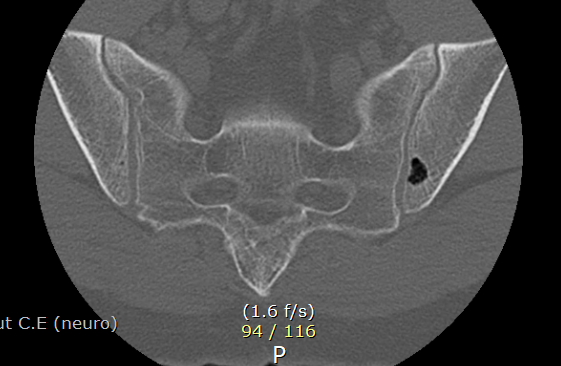

ct상 뼈에 구멍이 나보이는데 뭘까요?

현재 2달 조금 넘게 허리통증으로 외래진료 받는중인데 차도가 없어 ct를 촬영했는데 우연하게

골반뼈에 구멍 같은걸 발견했어요. 심각한 문제일까요?

선천적 이상일수도 있지만 이전 염증 및 감염 등의 흔적일 수도 있겠습니다.

뼈 안에도 물혹(낭종)이 생길 수가 있습니다. 허리 통증과는 큰 관련이 없을 수 있습니다. 치료도 대부분은 필요하지 않구요.

• CT 소견만 놓고 정확한 상태를 알기는 어렵지만 골반 뼈 부위에 비어있는 구멍이 있는 것으로 보이며 이외에 특이 소견은 보이지 않습니다. 허리 통증과 무관해 보이며 당장 큰 문제가 있다고 보기에는 애매합니다.